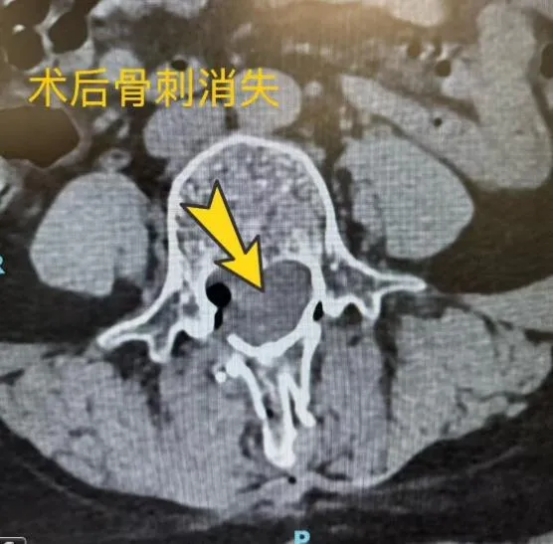

科室团队为患者制定了周密的手术方案。然而,手术中面对的远非单纯的脊髓栓系。同时患者存在“脊髓纵裂”——在腰椎L4水平,一个坚硬的骨刺如同“路障”般将脊髓一分为二,形成了两条独立的脑脊液循环通道。这使得手术难度陡增:不仅要解除终丝的牵拉,还需在极为狭小的空间内,精细磨除这道“骨墙”,并小心翼翼处理与之相连的、横亘在脊髓中间的复杂畸形结构。

术中,郭清保主任、蒋帅主治医师与王振华主治医师在显微镜下协同操作,如同进行一场穿越神经雷区的精密排险。他们以极大的耐心耗时磨除骨棘,再轻柔分离、处理脊髓内的异常连接,每一步都如履薄冰,最终成功完成了脊髓栓系松解及畸形矫治。

术后,复查骨刺消失,患者下肢疼痛有所缓解,步行能力稳步改善,恢复顺利。此例高难度复合型手术的成功,标志着神经外科二病区团队在复杂脊柱脊髓病变的显微外科处理上达到了新的高度。